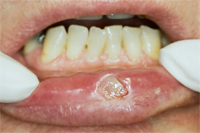

Die untere Bildserie beschreibt die Entfernung eines Hämangioms auf der Unterlippe eines 72 Jahre alten Patienten. Ein Hämangiom (Blutschwämmchen) ist ein embryonaler Tumor mit Endothelproliferation und sekundärer Ausbildung von Gefässlumen. Ein Herausschneiden war bei der gegebenen Grösse notwendig. Durch das Alter des Patienten und durch die empfindliche Lokalität des Hämangioms an der Lippe ist ein minimalinvasiver Eingriff mit schneller Wundheilung essentiell. Dies wird durch eine Laserbehandlung garantiert (Abb. 14-16).

Das herausgeschnittene Hämangiom wurde zwecks Untersuchung auf Malignität (bösartiger Tumor) ans Pathologische Institut der Uni Zürich geschickt. Es konnte als gutartig eingestuft werden.